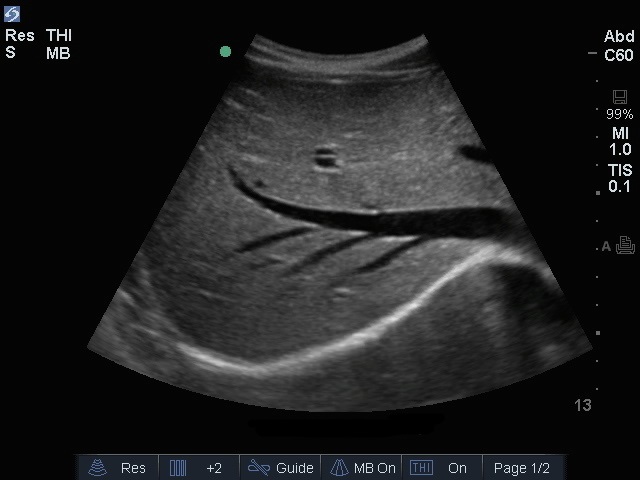

肝静脈画像